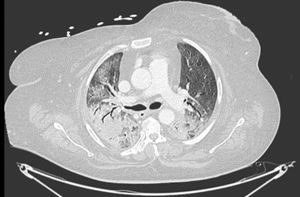

Pneumomediastinum (PM) is a condition where the air is present in the mediastinum. Free air leaks from ruptured alveoli, dissecting along the bronchovascular sheaths towards the mediastinum. PM, as seen on chest CT, elevates the mediastinal pleura and can extend into the neck or chest wall.14 One of the first signs that simulate a pneumomediastinum is the Mach band effect. This optical effect at the margin between areas of faintly different density15 can mimic various other pathologies (pneumopericardium, fracture), and makes it possible to suspect PM in COVID-19 patients. Non-traumatic PM is a rare complication of COVID-19 pneumonia.16 Its development in COVID-19 infection is also considered a possible indicator of disease worsening, which may be or not be associated with invasive ventilatory support. Spontaneous PM seemed to be a frequent complication of severe acute respiratory syndrome (SARS).17 In 2004, a high peak LDH level of 863 IU/L had been correlated with spontaneous PM in SARS patients, likely due to significant remodeling of the lung tissue causing leakage and vessel wall dissection.17 Most patients with PM had lung involvement higher than 50% at the moment of the diagnosis,18 corroborating the increased risk of rupture and PM development. This study aimed to evaluate the association between baseline serum LDH levels and COVID19 lung necrosis outcome based on the extent of lobar involvement and PM development.

In our study, CT was used to identify and confirm spontaneous PM and PM relative to mechanical ventilation. The scannographic signs of PM relied on the anatomical region occupied by the air as it exits the mediastinum.20 (Figs 1, 2).